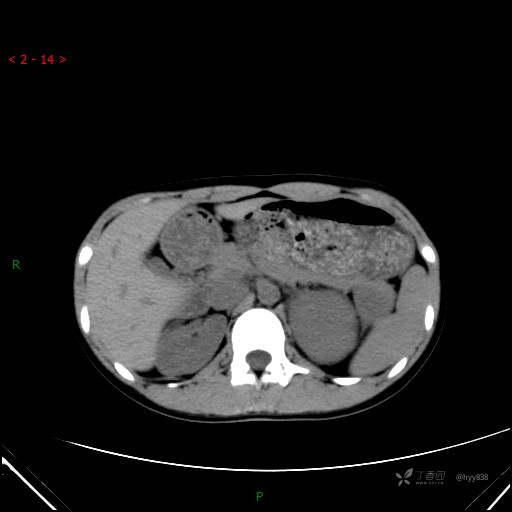

增强静脉期